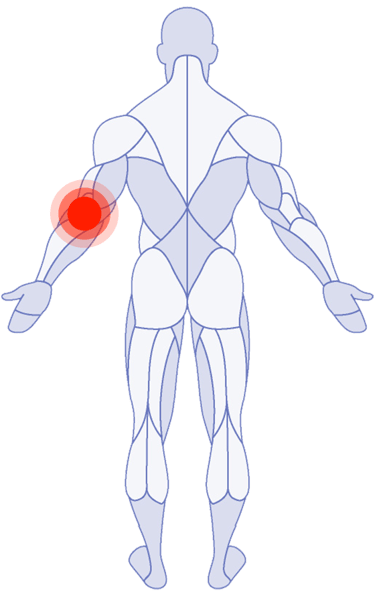

Shoulder Pain

Tricep Pain

Where Do You Need Attention?

Use the latest research in physical therapy to work better, play better and spend more time on what really matters.